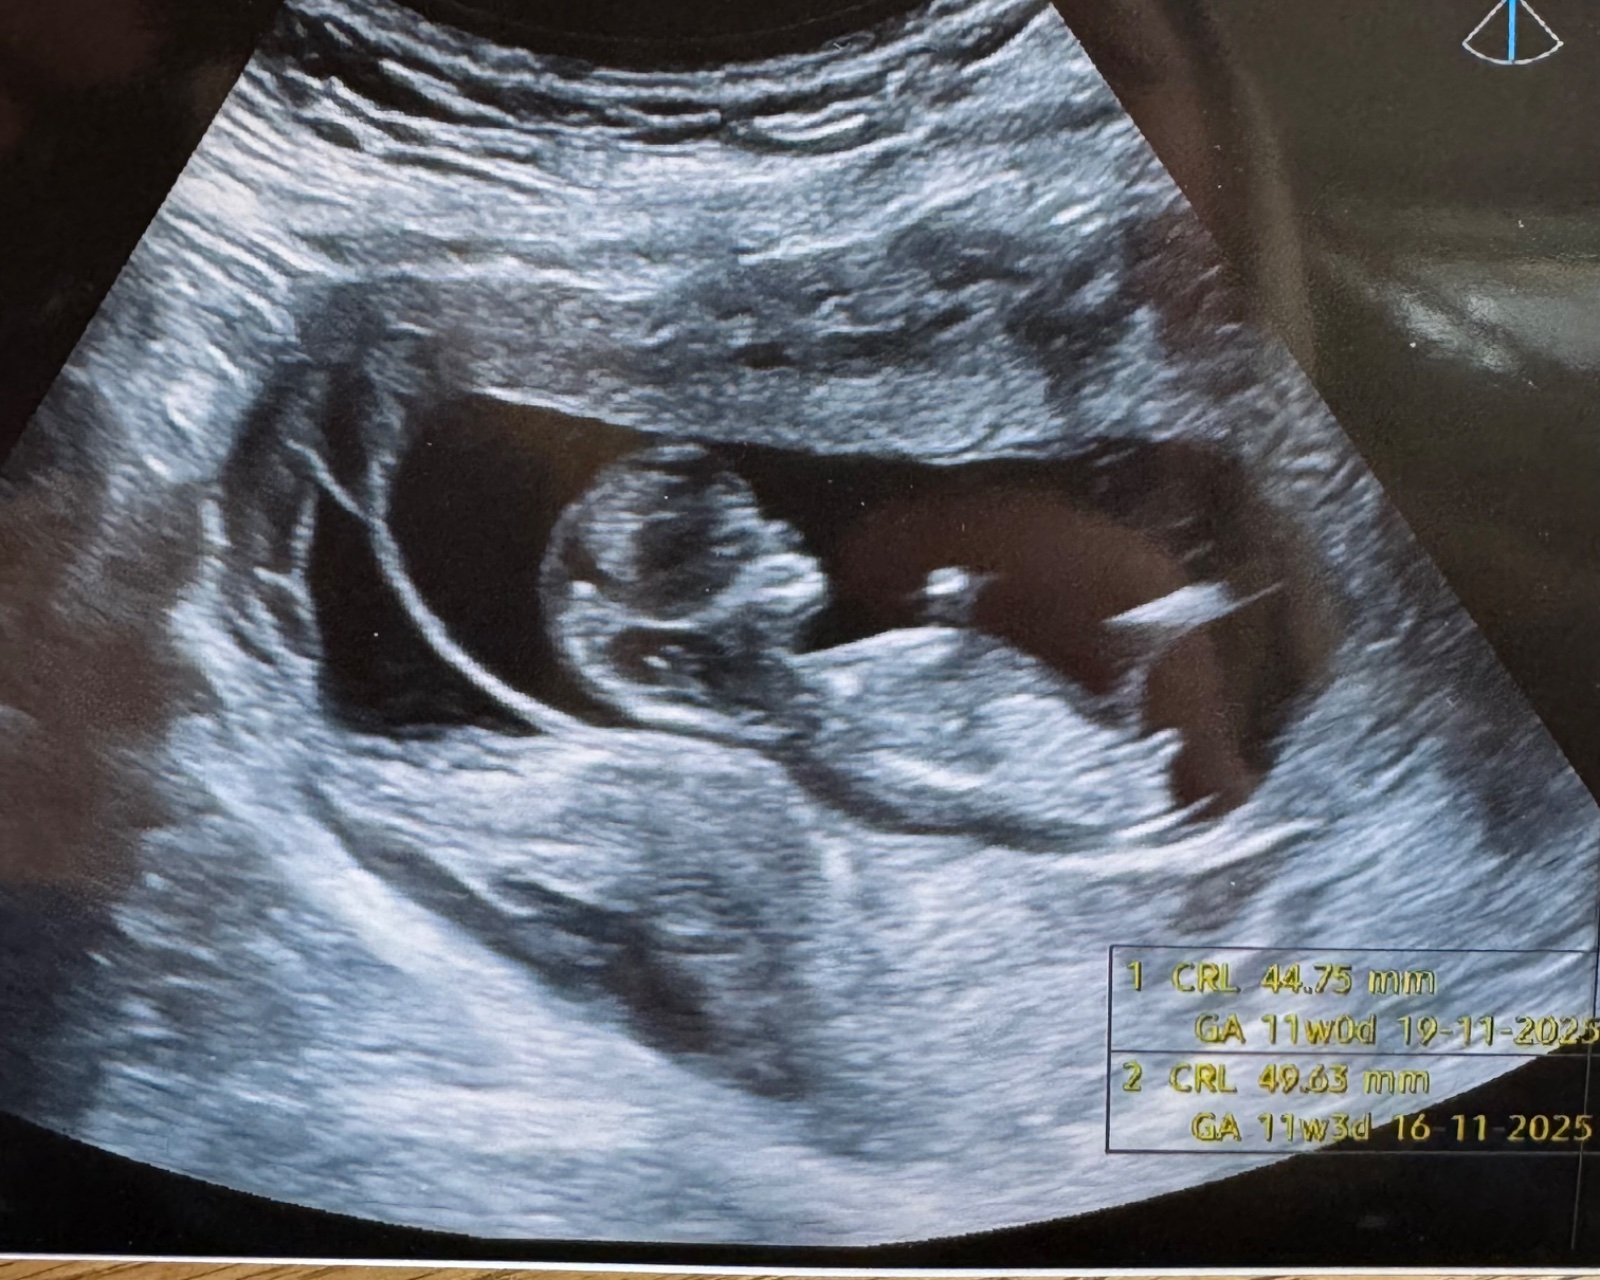

jde prosím poznat pohlaví miminka?

omlouvám se, ale posuzovat pohlaví z jedné či několika fotografií v prvním trimestru je poměrně nepřesné a u velké části plodů nelze vůbec. Nenahradí to vyšetření v reálném čase a i to má velké limitace. Vydržte do pozdějších fází, kdy to lze v naprosté většině případů odhadovat téměř stoprocentně.